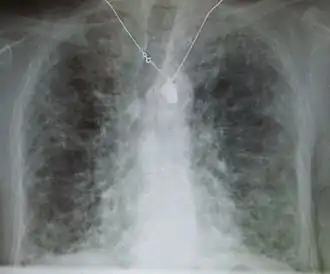

Longfibrose, ofwel bindweefselvorming in de longen, is een chronische aandoening waarbij het longweefsel minder goed functioneert. Het is een zeldzame ziekte waarbij de capaciteit van de long om zuurstof op te nemen vermindert. Dit heeft tot gevolg dat de betrokkene kortademig wordt, snel moe is en weinig energie heeft.[1]